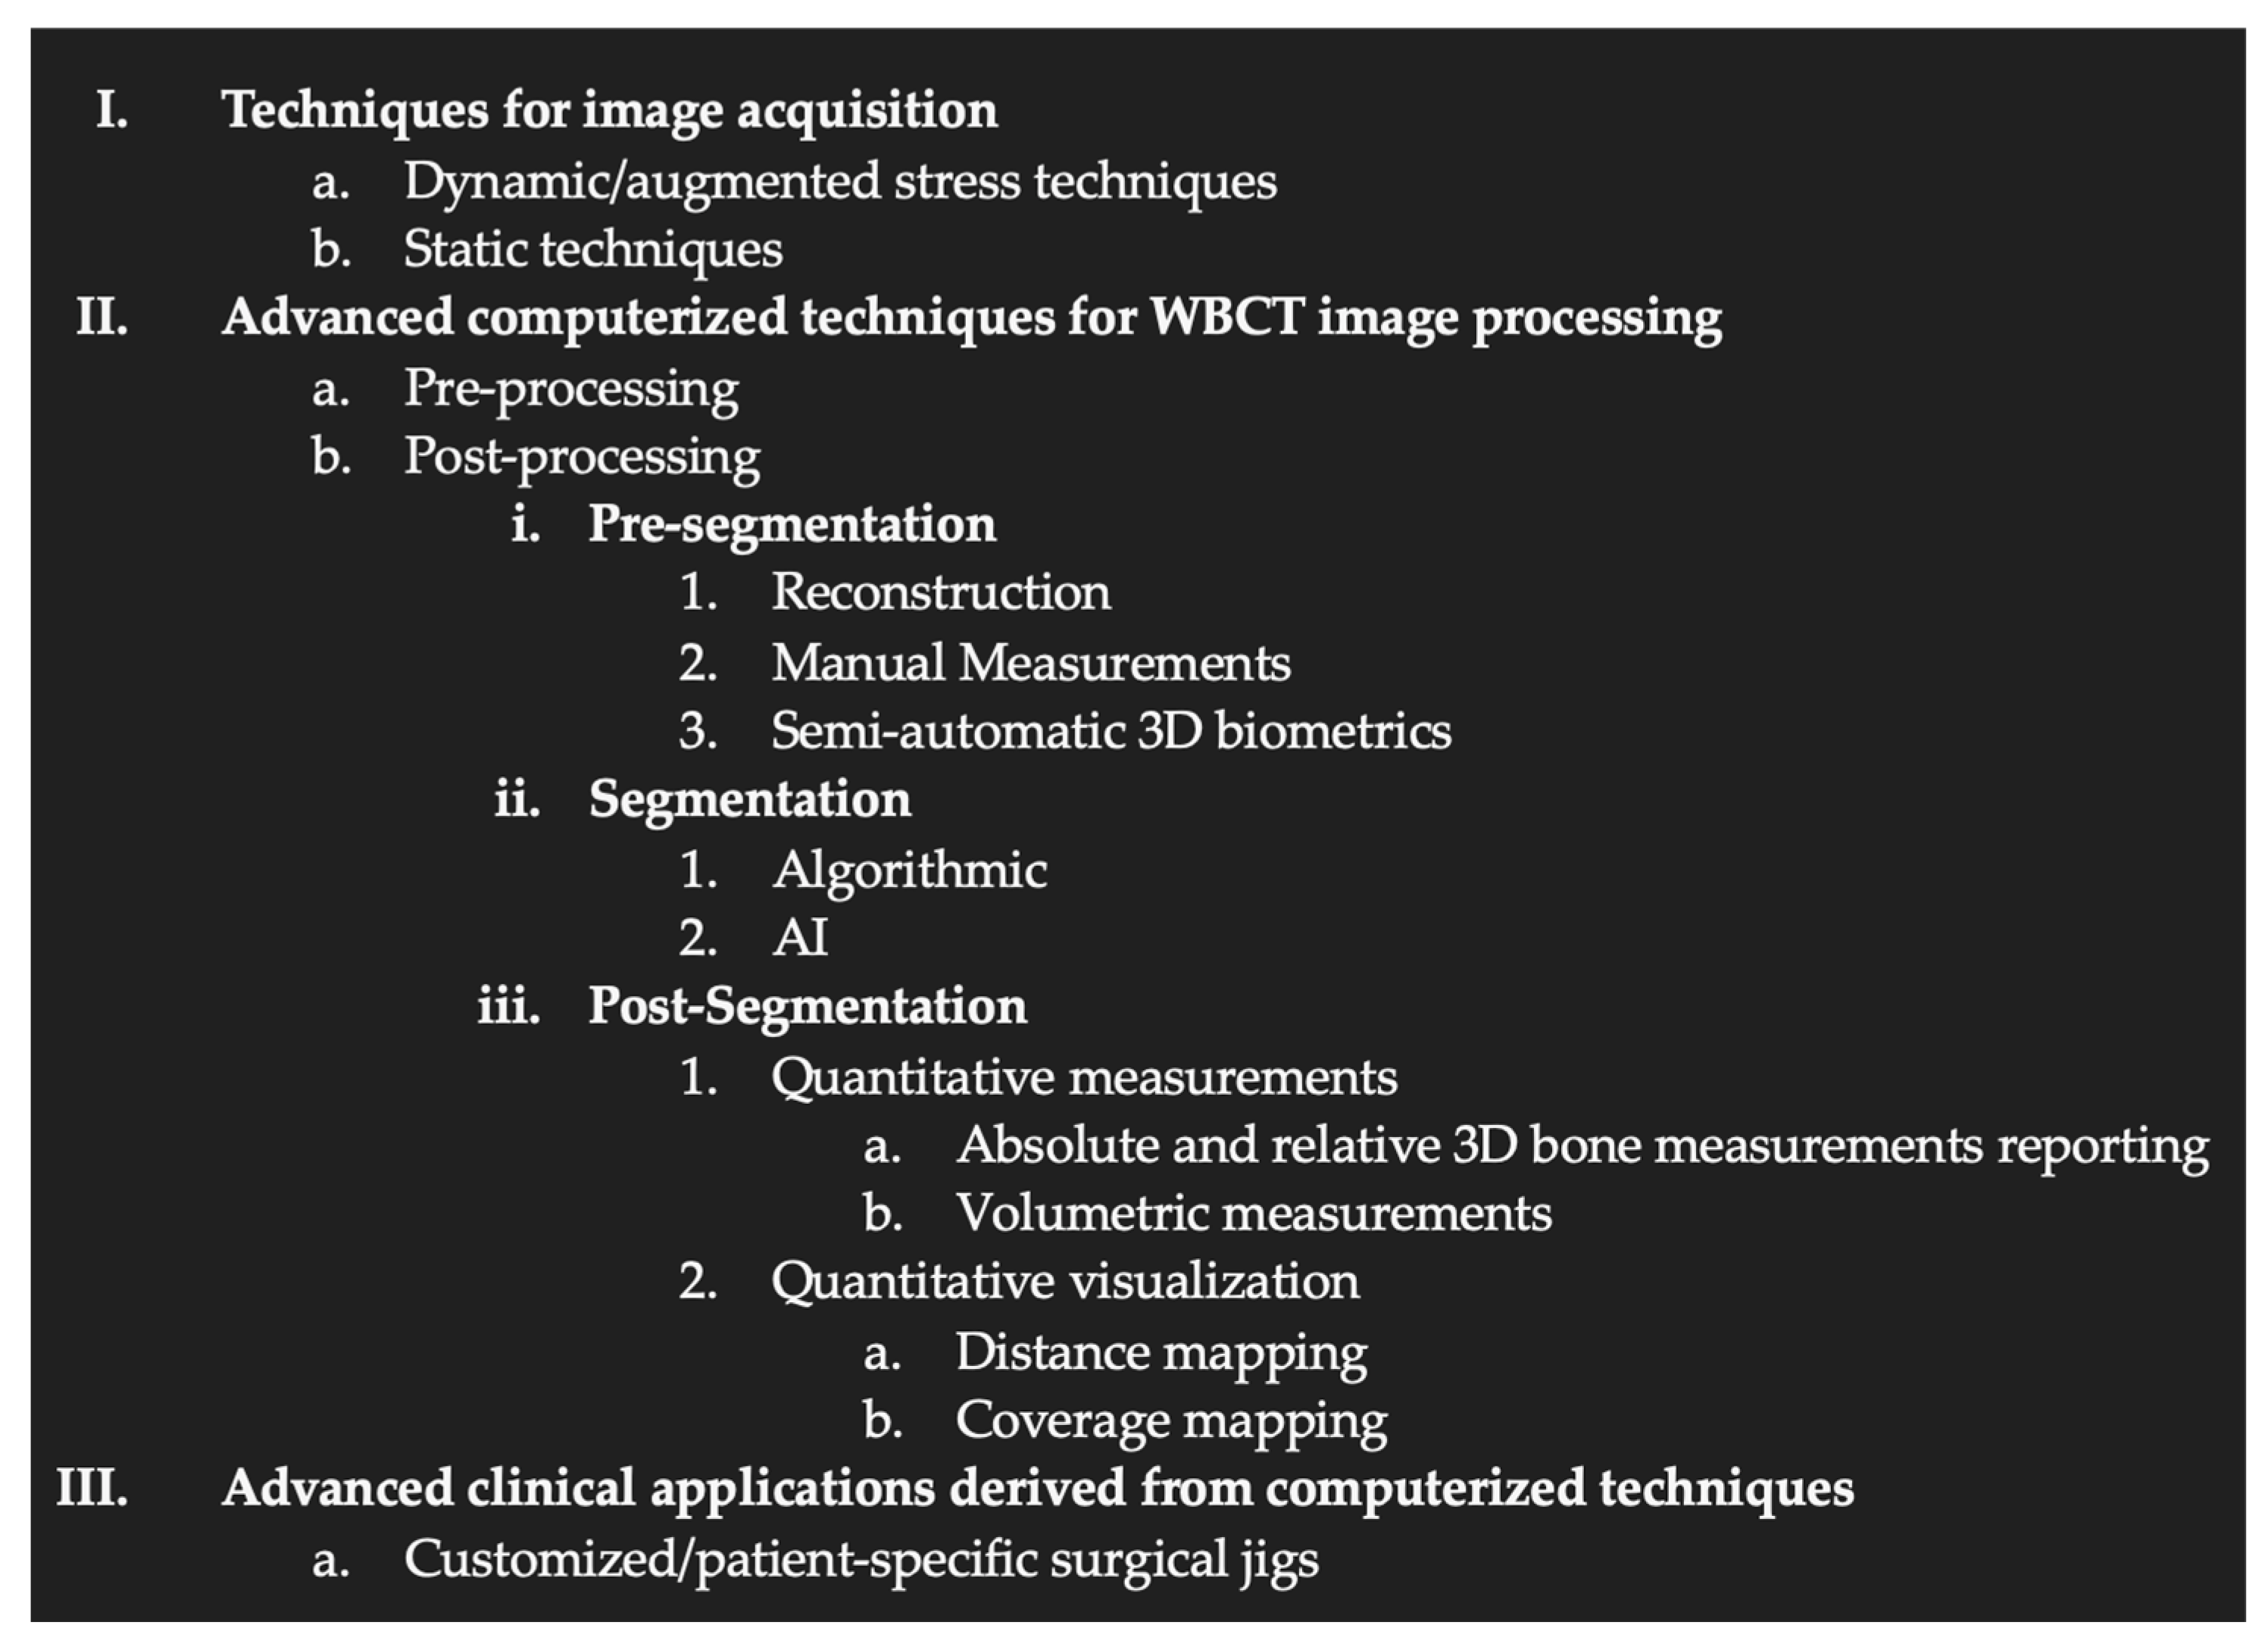

3.3. Organization of the WBCT Workflow: Proposal for a Classification of Recent Innovations

- Techniques for image acquisition

- Computerized techniques for image processing

- ◦

- Pre-processing (processing of the raw data before image rendering)

- ▪

- Metal artifact reduction

- ▪

- Movement Artifact reduction

- ◦

- Post-processing

- ▪

- 3D biometric techniques without segmentation

- ▪

- 3D biometric techniques with segmentation (manual, semi-auto or auto)

- Advanced clinical applications derived from computerized techniques

4.2.1. Description of Techniques for Image Acquisition

4.2.2. Description of Advanced Computerized Techniques for Image Processing

Pre-Processing

Post-Processing

- Pre-Segmentation

- Reconstruction

- 3.

- Manual Measurements

- 4.

- Semi-Automatic 3D Biometrics

- 5.

- Segmentation

Post-Segmentation

4.2.3. Description of Techniques for Advanced Clinical Applications Derived from WBCT Computerized Techniques